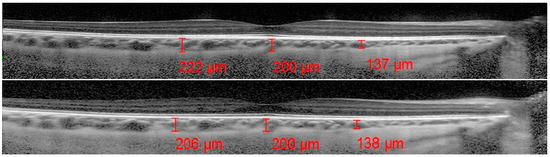

2.3. OCT Analysis